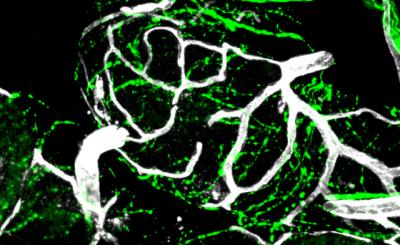

In the current study, the researchers used a mouse model of prostate cancer to determine precisely how nerves within connective tissue drive tumor growth. After being released by nerve fibers, norepinephrine binds to receptors on endothelial cells that line the inner surface of blood vessels. The researchers found that the binding of norepinephrine to those receptors triggers an "angio-metabolic switch" that changes how cells metabolize glucose. To make new blood vessels, the endothelial cells--which ordinarily use oxidative phosphorylation to obtain energy from glucose--were now relying almost exclusively on glycolysis. Using glycolysis to metabolize glucose is a phenomenon that had previously been observed in cancer cells.

To confirm norepinephrine's role in triggering this metabolic switch, the researchers deleted a gene in their animal model that codes for norepinephrine's receptor on vessel cells, thereby eliminating norepinephrine's binding target. They then observed that cells lacking the receptor were using oxidative phosphorylation rather than glycolysis. As a result, the formation of new vessels was inhibited.

"Oxidative phosphorylation generates more energy than glycolysis," says Dr. Frenette. "It may seem counter-intuitive, but this energy boost provided by oxidative phosphorylation diminishes endothelial cell function and inhibits angiogenesis--the formation of new blood vessels that sustains tumor growth." In Dr. Frenette's mouse model of prostate cancer, stimulation from norepinephrine released by nerves had allowed endothelial cells to maintain use of glycolysis, enabling the rapid progression of prostate cancer from a low-grade precancerous stage to a high-grade malignant stage.